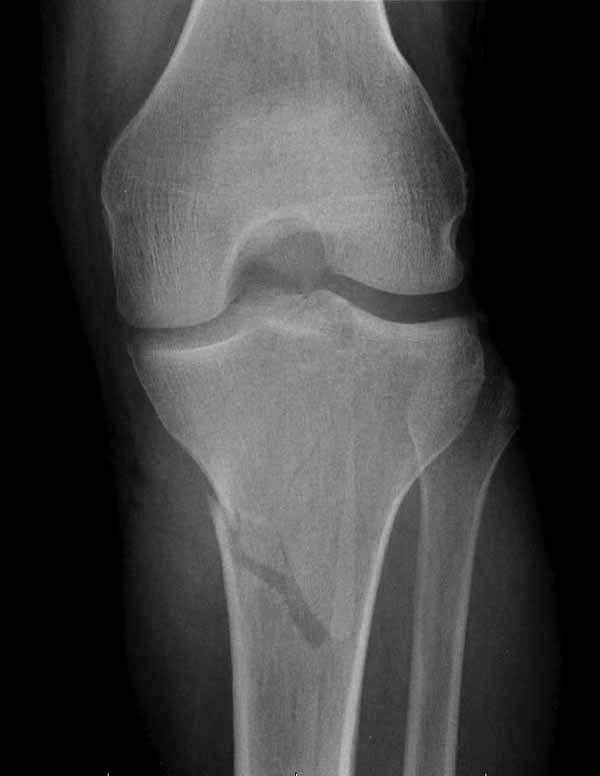

В приложении этапы фиксации пластиной Synthes для плеча при переломе медиального мыщелка.

Имя     : 4 medial column tibial plateau.JPG

Тип     : image/jpg